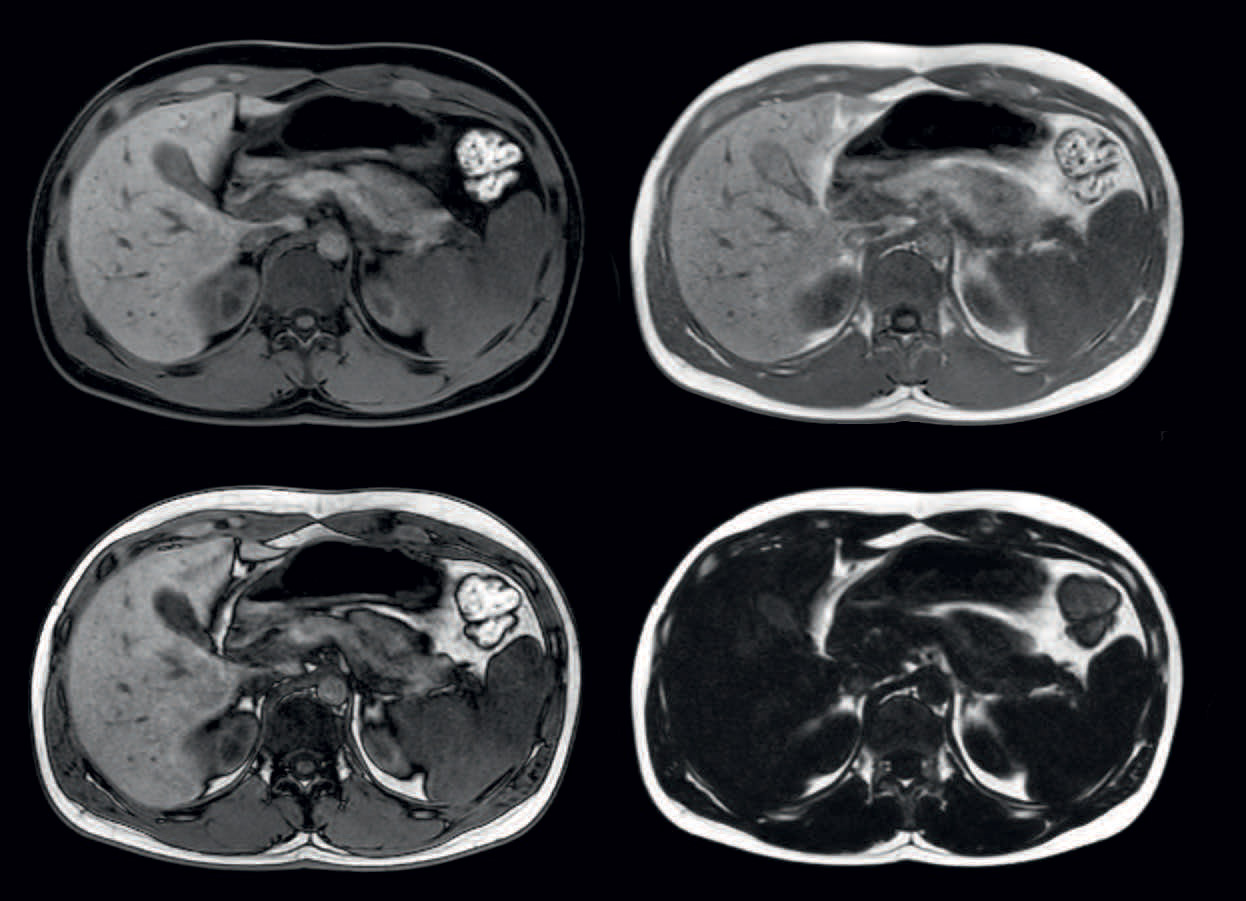

Four different contrasts in one breathhold

mDIXON provides four different contrasts in one scan: water, fat, in-phase and out-phase images. Voxels 1.3 x 1.5 x 2.5 mm, high dS SENSE acceleration factor, breathhold 16 seconds.